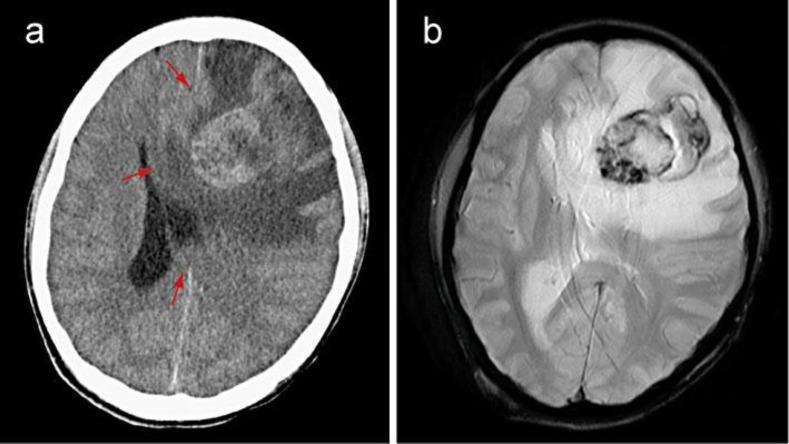

Intracranial metastasis of hepatocellular carcinoma (HCC) is rare, but has an extremely poor prognosis. We report a case with successful surgical removal of intracranial metastasis of HCC. A 32-year-old man was admitted to our hospital with severe vomiting. He had been followed for liver cirrhosis due to hepatitis B virus infection and received a right hepatic trisectionectomy for HCC 1 year earlier. For the recurrence of HCC, sorafenib had been administered 6 months before admission. On admission, he exhibited consciousness disturbance, which gradually worsened. Two days later, both computed tomography and magnetic resonance imaging revealed an intra-axial tumor with perifocal edema and hemorrhage in the left frontal lobe. The tumor was successfully removed by craniotomy and pathological examination revealed that it was composed of moderately differentiated HCC cells. The day after surgical resection of the tumor, his consciousness returned to normal. Subsequently, he was treated with hepatic arterial infusion chemotherapy with 5-fluorouracil and cisplatin using an implanted port-catheter system. Surgical resection of intracranial metastasis of HCC would be important and meaningful in some cases.

肝细胞癌(HCC)的颅内转移罕见,但预后极差。我们报告一例成功手术切除HCC颅内转移灶的病例。一名32岁男性因严重呕吐入院。他因乙型肝炎病毒感染导致肝硬化,1年前接受了HCC右半肝切除术。因HCC复发,入院前6个月给予了索拉非尼治疗。入院时,他出现意识障碍,且逐渐加重。两天后,计算机断层扫描和磁共振成像均显示左额叶有一个轴内肿瘤,伴有瘤周水肿和出血。通过开颅手术成功切除了肿瘤,病理检查显示其由中度分化的HCC细胞组成。肿瘤手术切除后的第二天,他的意识恢复正常。随后,使用植入式导管系统对其进行了5-氟尿嘧啶和顺铂肝动脉灌注化疗。在某些情况下,手术切除HCC颅内转移灶具有重要意义。